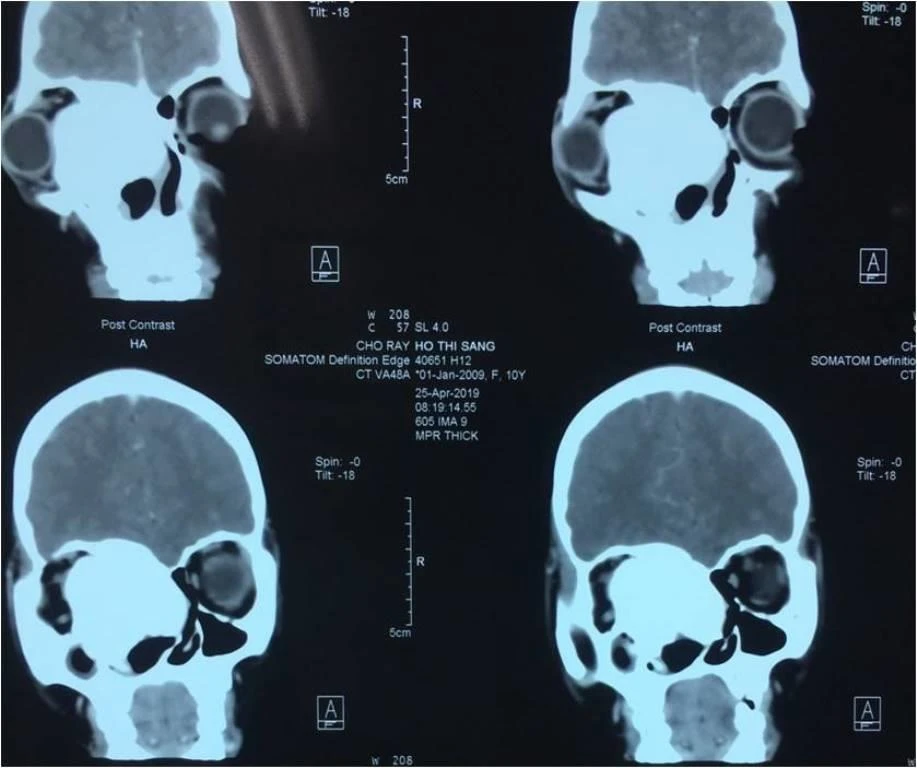

Theo BS Công, bé gái nhập viện với tình trạng lồi mắt phải, dãn khoảng cách 2 mắt, thị lực mắt phải chỉ còn 1/10 gây biến dạng khuôn mặt. Hình chụp CT-scan cho thấy bé có khối u sợi sinh xương khổng lồ hốc mũi xâm lấn mắt và nền sọ trước.

Khối u của bé gái trên phim chụp CT-Scan. Ảnh: HL